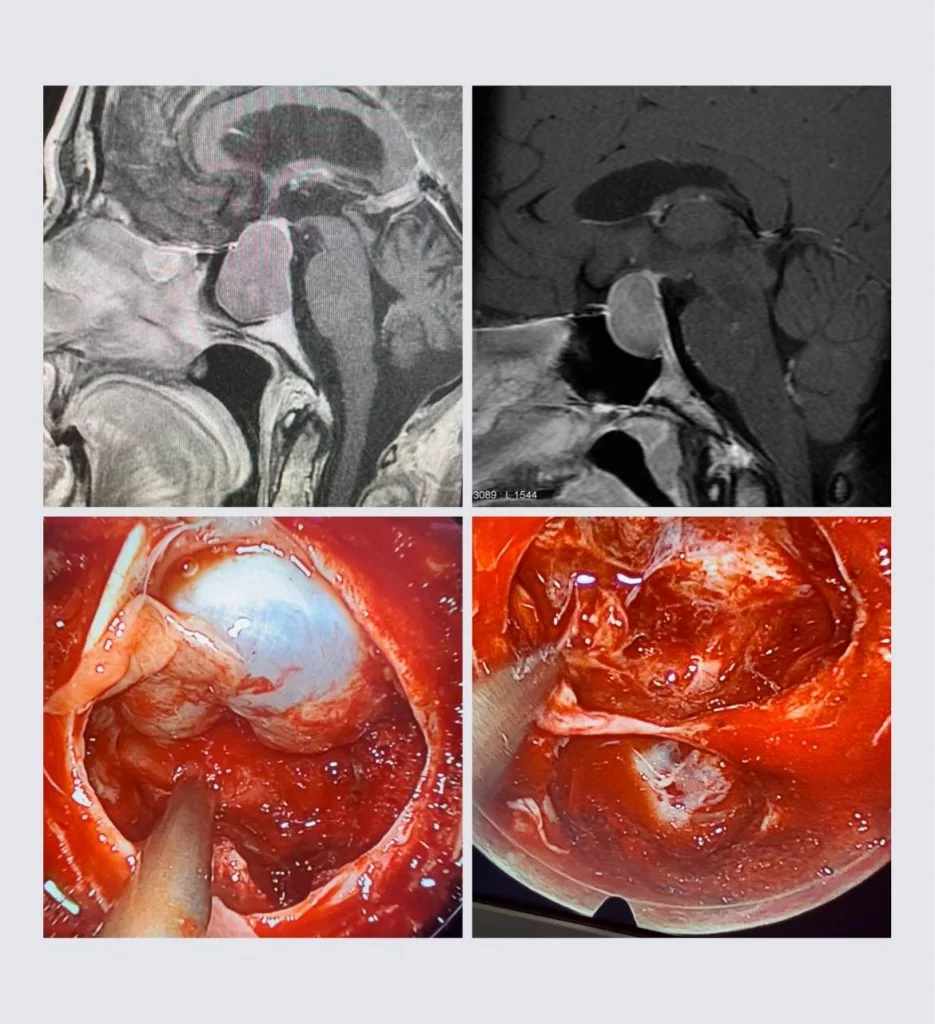

Στην ανωτέρω εικόνα απεικονίζονται δύο διαφορετικά αδενώματα υπόφυσης με το ίδιο αποτέλεσμα: την ολική αφαίρεση του όγκου. Εφαρμόστηκε η διαρρινική ενδοσκοπική προσπέλαση. Σύγκλειση με αιματούμενο κρημνό τύπου Hadat (προσωπικό αρχείο νευροχειρουργού Π. Σταυρινού).